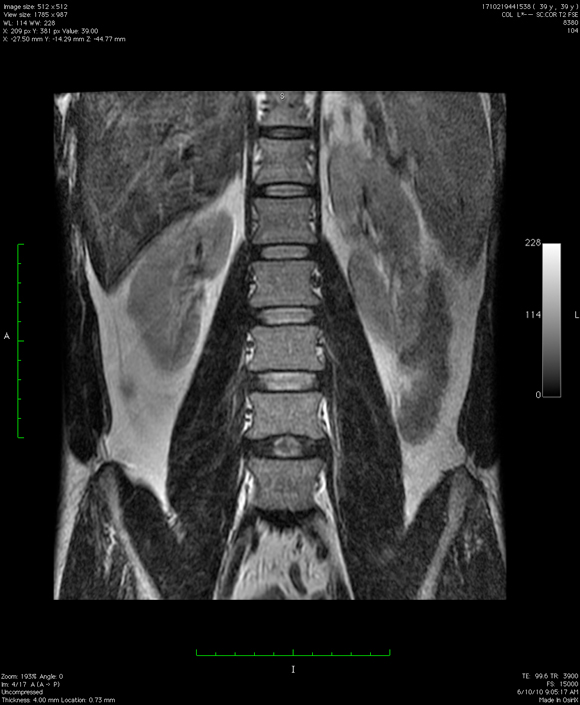

p.s. Am completat cu o panoramica dentara, cu un RMN la coloana si cu doua radiografii cervicale. Seria continua !